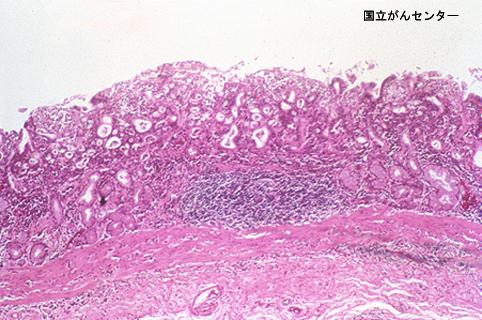

疾患(病理主体)の分類悪性上皮性腫瘍/腺癌

部位(臓器別)胃(部位)/体部

検査方法ミクロ

腫瘍の肉眼分類0型(表在型)/IIb型(IIb+IIc)

病変の最大径(ミリ)40以上

腫瘍の深達度sm